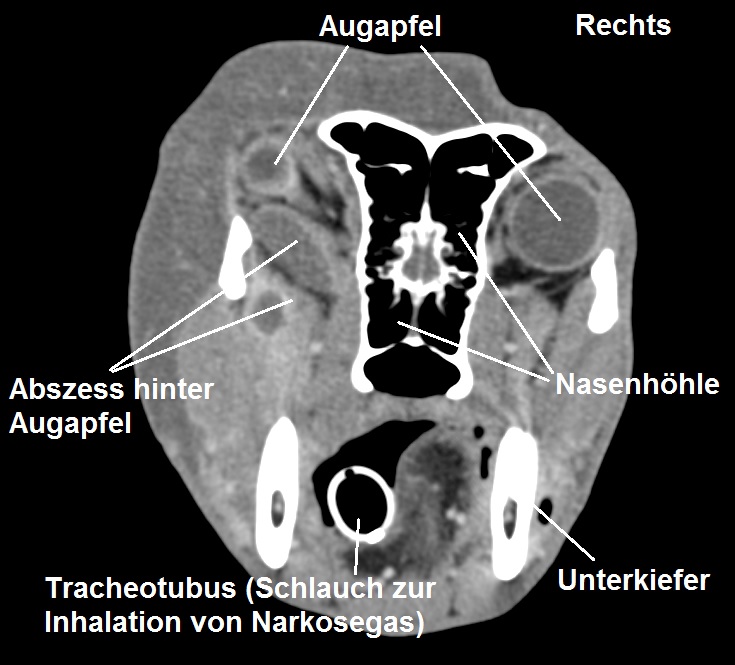

Unter Narkose wird am gleichen Nachmittag von Juci ein Computertomogramm (CT) des Kopfes angefertigt. Das dreidimensionale Röntgenbild zeigt, dass sich im Schädel des Hundes linksseitig ein Abszess gebildet hat, welcher aus mehreren Kammern besteht, die Augenhöhle hinter dem Augapfel durchquert und vom Gaumen bis in die Kaumuskulatur der Kopfoberseite reicht.

Die Diagnose konnte mittels Computertomografie (CT) gestellt werden. Hierbei wird quasi eine Serie von Röntgenbildern angefertigt, welche den zu untersuchenden Körper von verschiedenen Seiten darstellen und so ein dreidimensionales Bild errechnen. Eine ähnliche Untersuchungsmethode ist das MRT (Magnetresonanz-Tomografie), bei welchem mithilfe einer anderen Methode ebenfalls ein dreidimensionales Bild erstellt werden kann. Beide Untersuchungsmethoden müssen beim Tier in Narkose durchgeführt werden, weil absolutes Stillliegen vonnöten ist; je nach untersuchter Region belaufen sich die Kosten auf mehrere hundert bis über tausend Franken. Die grossen Anschaffungskosten bedingen, dass die Geräte sowohl in der Human- als auch Veterinärmedizin nur von grossen Kliniken oder Spezialistenpraxen betrieben werden.